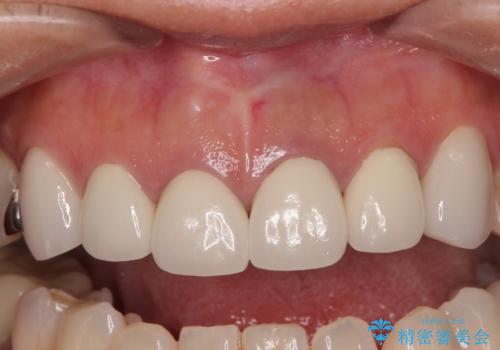

上顎前歯の根尖病変に痛みがありましたが、既に前歯が補綴治療済みであっため、外科的歯内療法(歯根端切除術)を行うことで解決することとしました。